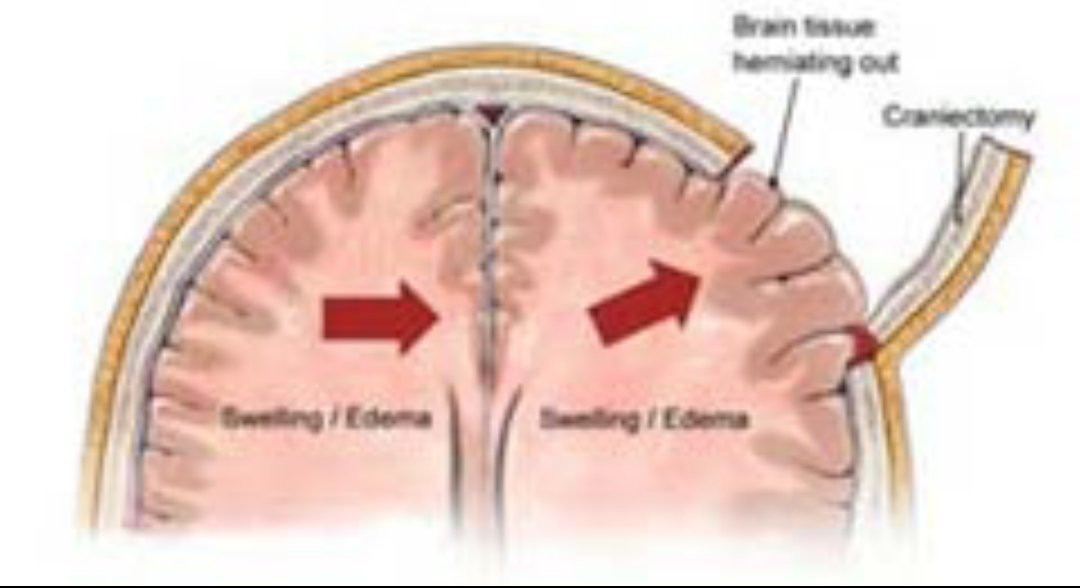

💥هنالك حالات يزداد فيها الضغط داخل الجمجمه

💥بسبب

🧠تجمع السوائل

🧠غزارة النزيف

🧠 كبر حجم التجمع الدموي

💥ولان العظم لايتمدد

فقدرته محدده لاستيعاب الحجم الزائد

فنضطر بشروط معينه

🧠اعطاء علاجات ومدرات

🧠وضع أنبوب تصريف

🧠ازالةجزء من الجمجمه

💥هنالك حالات يزداد فيها الضغط داخل الجمجمه